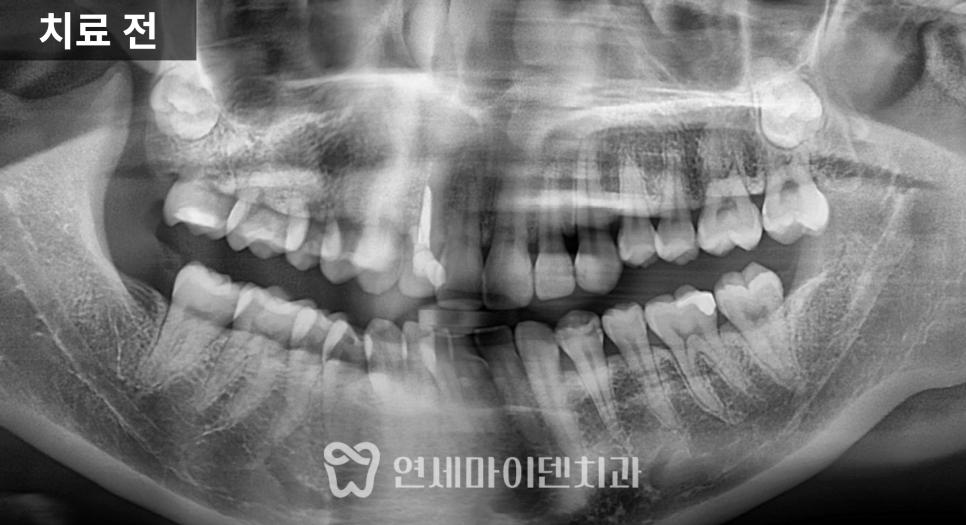

해당 치아는 왼쪽 아래 어금니였고,

잇몸에서 고름이 배출되는 통로가 형성되어 있는 상태였습니다.

엑스레이를 확인해보니

일반적인 포스트가 아니라

캐스트 포스트가 깊게 삽입되어 있었고,

주변 신경치료 상태 역시

깔끔하게 마무리된 형태는 아니었습니다.

이러한 경우에는 단순 치근단 염증뿐 아니라

치근파절 가능성을 반드시 함께 고려해야 합니다.